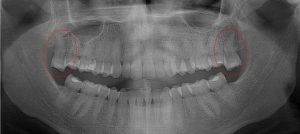

This 19 year old patient has all four 3rd molars present (circled). Only the upper left 3rd molar has fully erupted. The lower left 3rd molar is partially exposed and decaying while the lower right soft tissue impacted, both requiring extraction. Note the double crown on the upper right third molar.